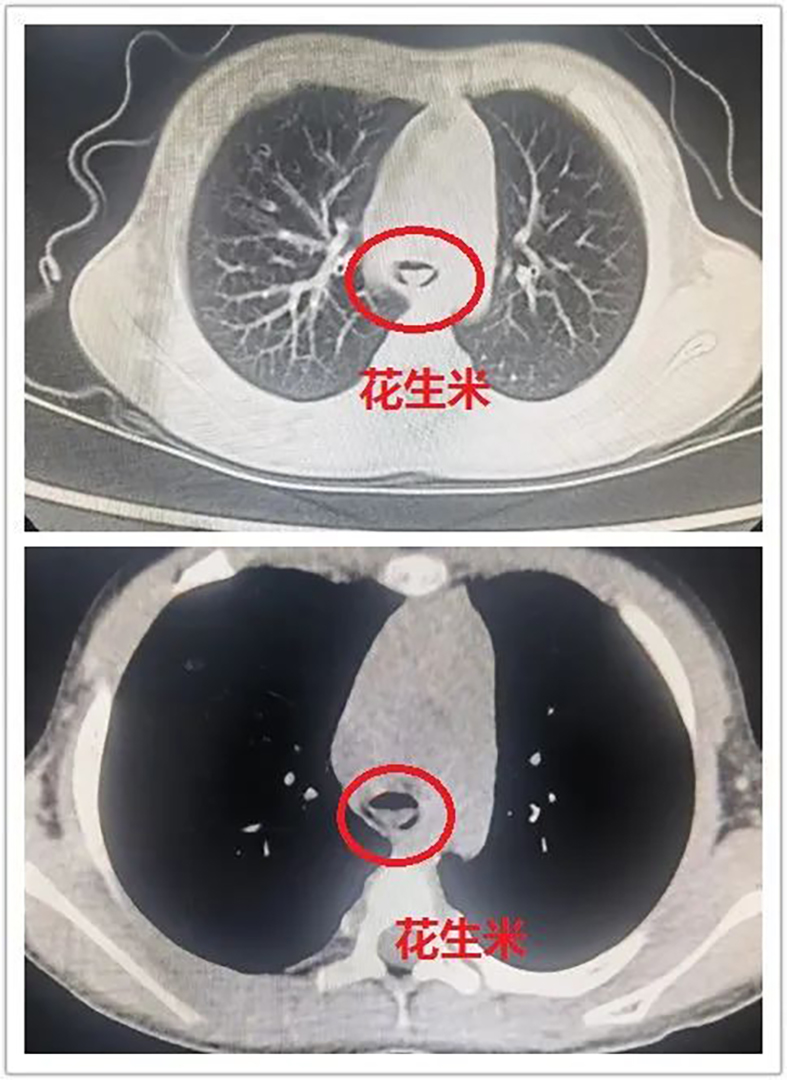

2月8日,一名4岁女童气道内呛入花生米,紧急到山西省医院协会理事单位——晋城大医院呼吸与危重症医学科就诊,经紧急救治,患儿转危为安。

医生检查发现,花生米几近阻塞气道,患儿情况十分危急,即刻决定实施气管镜介入治疗。

在麻醉与围手术期医学科的密切配合下,一场静脉复合麻醉+喉罩下行经气管镜手术展开。很快,医生就从女童气道内取出花生米,让患儿转危为安。